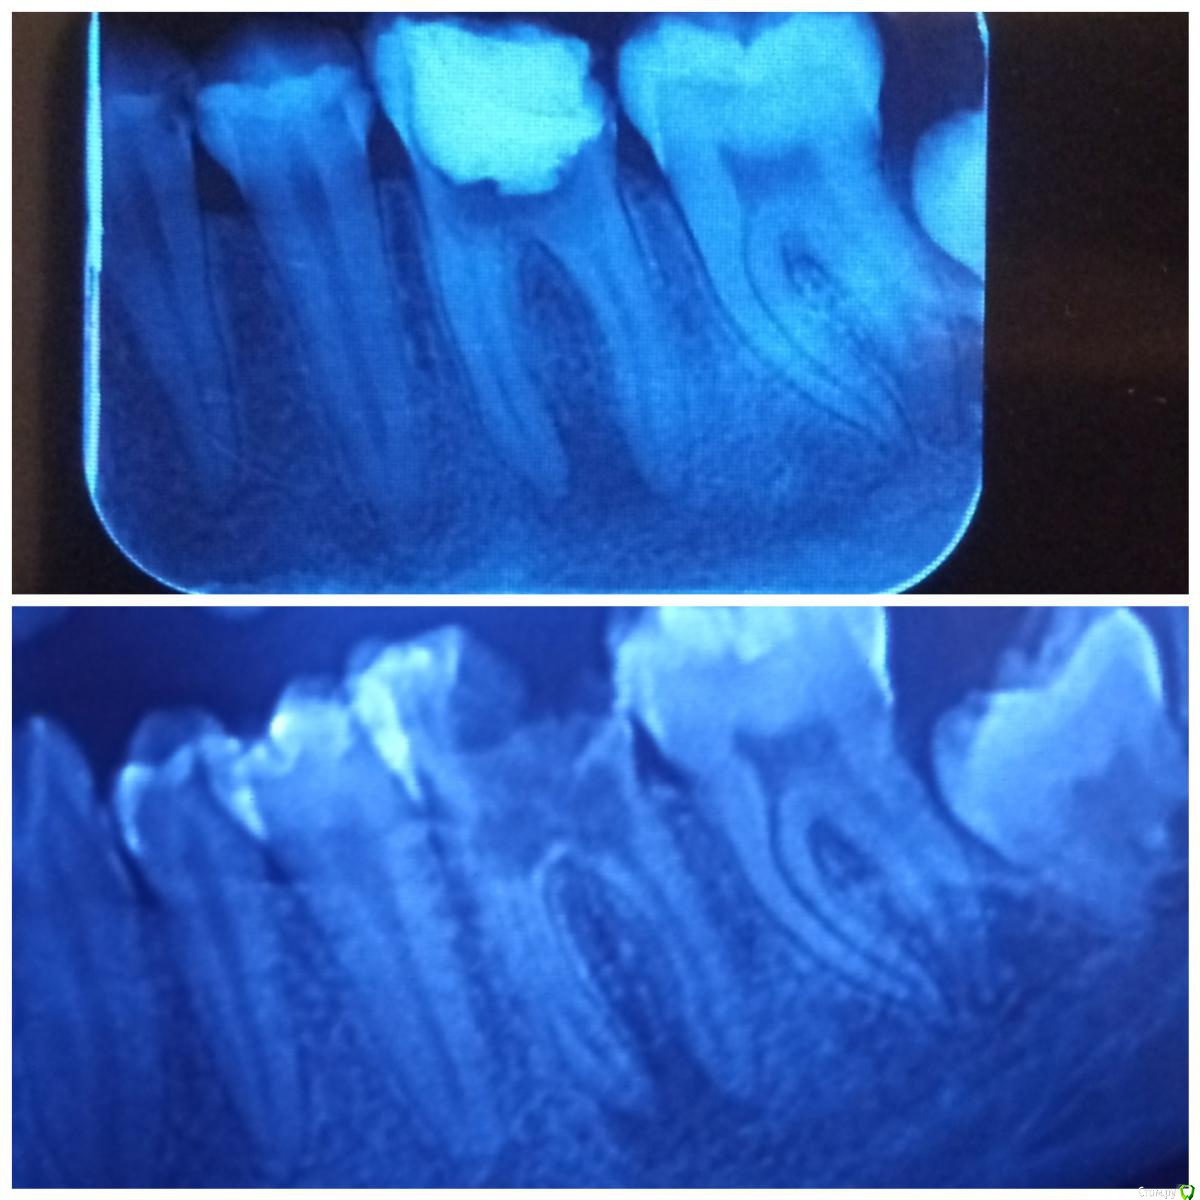

Studentic Опубликовано 24 ноября, 2019 Автор Поделиться Опубликовано 24 ноября, 2019 Снимок в верхней половине-после 4-5 недель на кальции. Есть положительная динамика, или все дело в разной контрастности снимков? Ссылка на комментарий

vse32 Опубликовано 24 ноября, 2019 Поделиться Опубликовано 24 ноября, 2019 4-5 недель это не те сроки, когда можно делать выводы о динамике. Хотя на снимках она вроде как есть. Ссылка на комментарий

DmitrySH Опубликовано 24 ноября, 2019 Поделиться Опубликовано 24 ноября, 2019 Да вроде там лучше, но кол-во дентина на фуркации очень настораживает 3 Ссылка на комментарий

Studentic Опубликовано 28 ноября, 2019 Автор Поделиться Опубликовано 28 ноября, 2019 Обтурация конечно не очень красиво получилась. Видимо у-файлом нарезал стенки канала. Буду наблюдать что будет дальше. Ссылка на комментарий